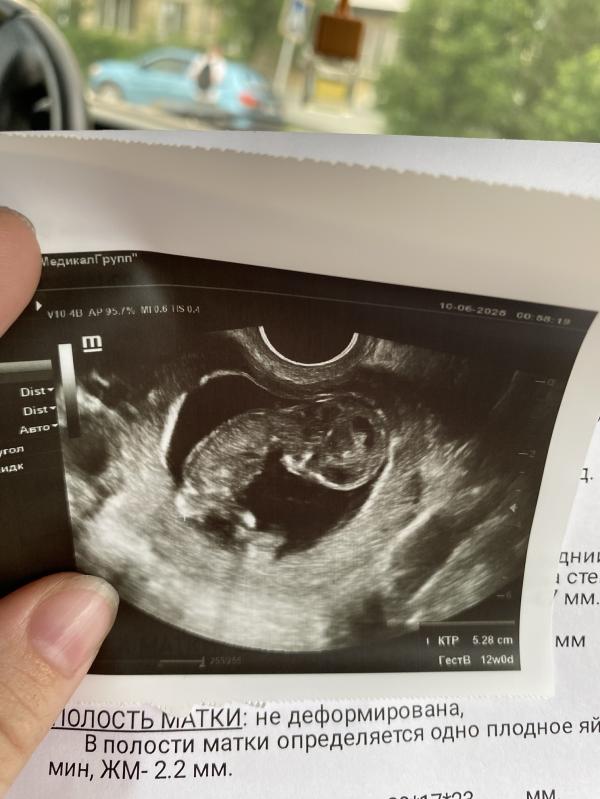

Добрый день ,в 11,6 делала узи .малыш так странно лежал ,ну он просто лежал ,сердцебиение 149 ,у кого так было ?врач сказала ему нравится значит так лежать ,ну он просто лежал #первыйпост